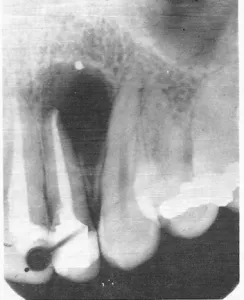

À la radiographie conventionnelle, le desmodonte se visualise comme une ligne radioclaire fine et régulière séparant :

- La surface radiculaire (radiopaque)

- La lamina dura (ligne radiodense longeant l’alvéole)

Selon PRICHAUD, une image d’épaisseur régulière est un signe de normalité. À l’inverse :

- Un élargissement de l’espace desmodontal évoque une surcharge occlusale, un traumatisme ou une parodontite apicale

- L’absence de l’espace desmodontal signe l’ankylose dento-alvéolaire